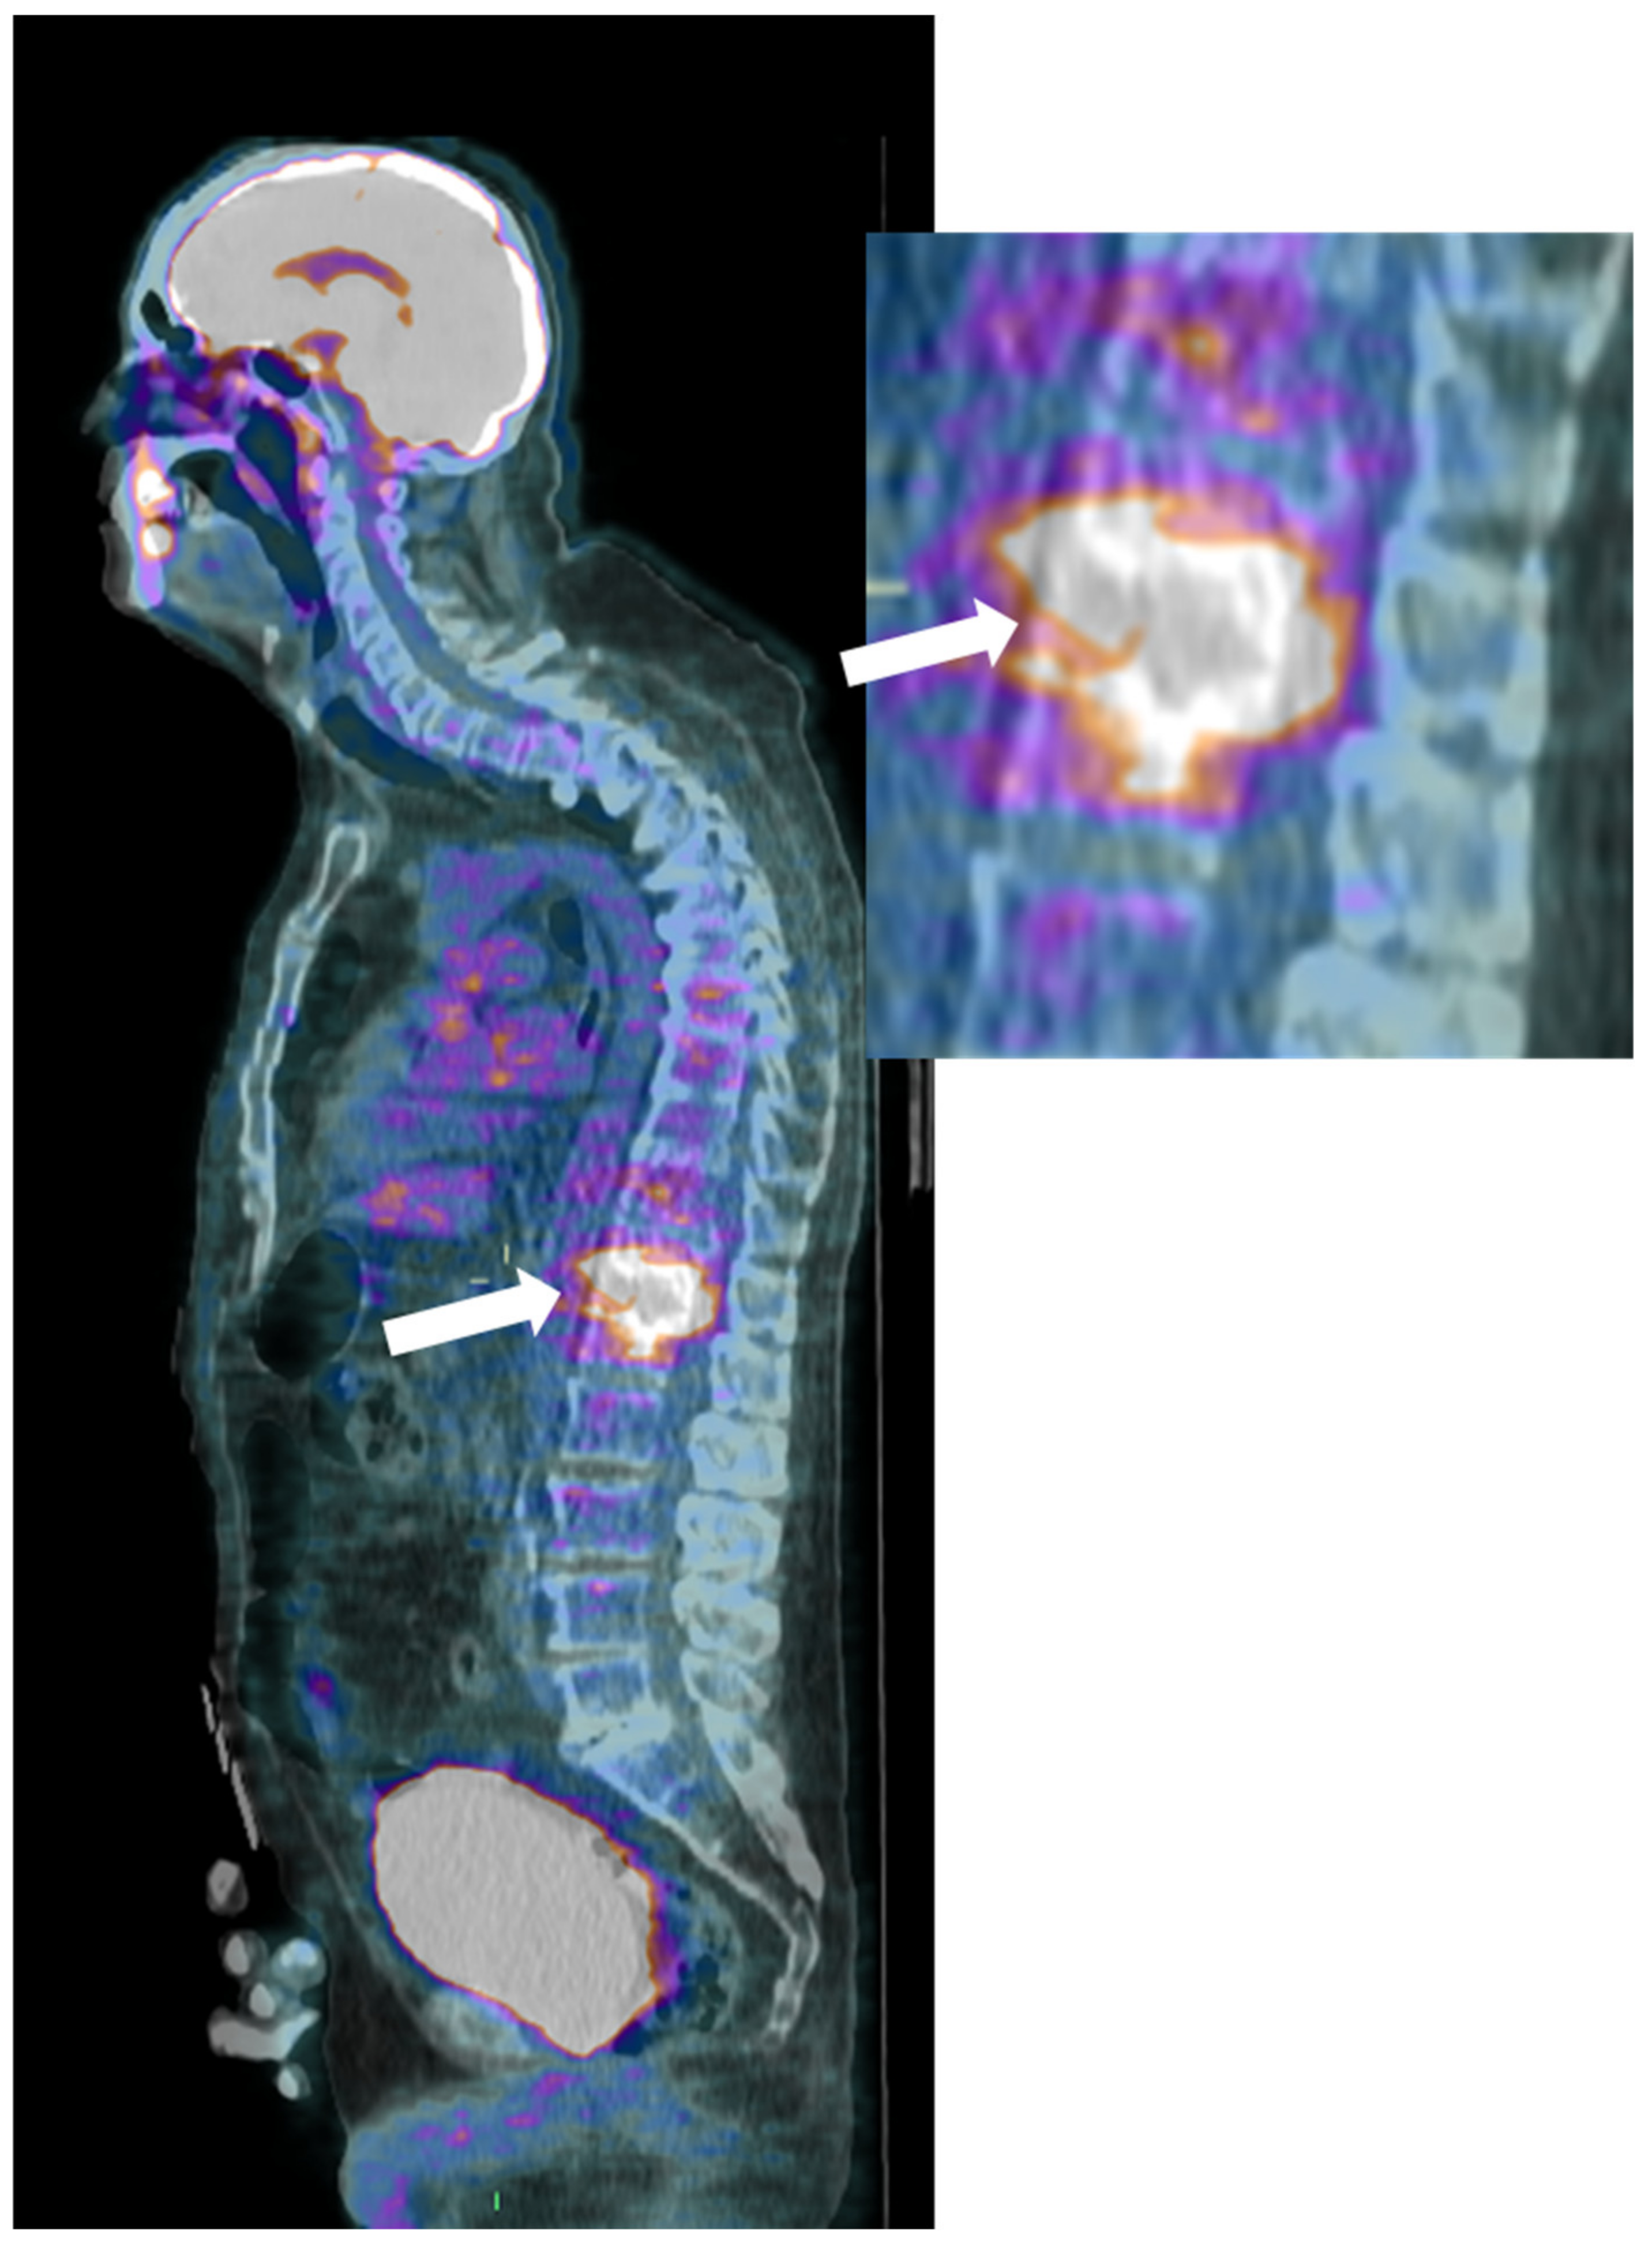

Finally, 18F-Fluorodeoxyglucose-positron emission tomography (18F-FDG-PET) is a sensitive and whole-body imaging tool, though lacking anatomical details; combining it with CT or MRI improves spatial resolution and aids in distinguishing infectious from degenerative abnormalities (Figure 5) [42,45].

Figure 5. (FDG) PET-CT, Sagittal reconstruction (magnification on the right) of a 72-year-old male with pyogenic spondylodiscitis of T12-L1 vertebrae. A high pathologic FDG uptake is detected in the disc and vertebral endplates (arrows).